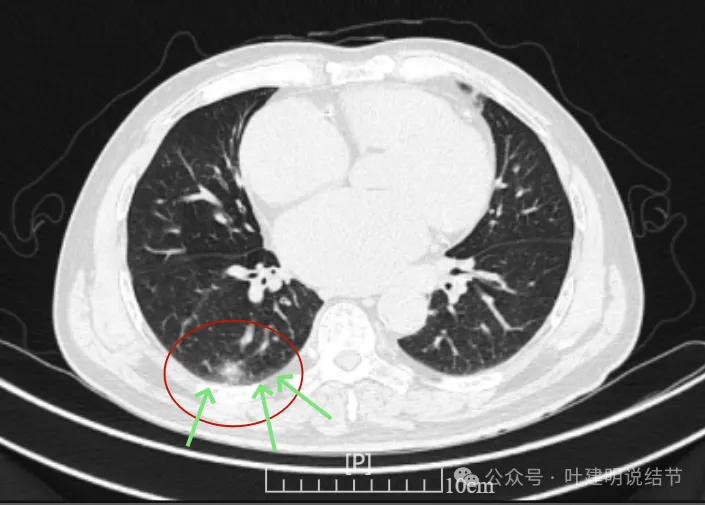

这是冠状位、矢状位与轴位的影像。

增强纵隔窗见病灶内部的密度好像低于周围区域,像坏死。

邻近胸膜无牵拉,灶内有低密度区,局部有点状液性密度。邻近胸膜较为广泛的增厚或胸膜反应。

病灶与胸膜接触面宽,病灶内部密度较低。